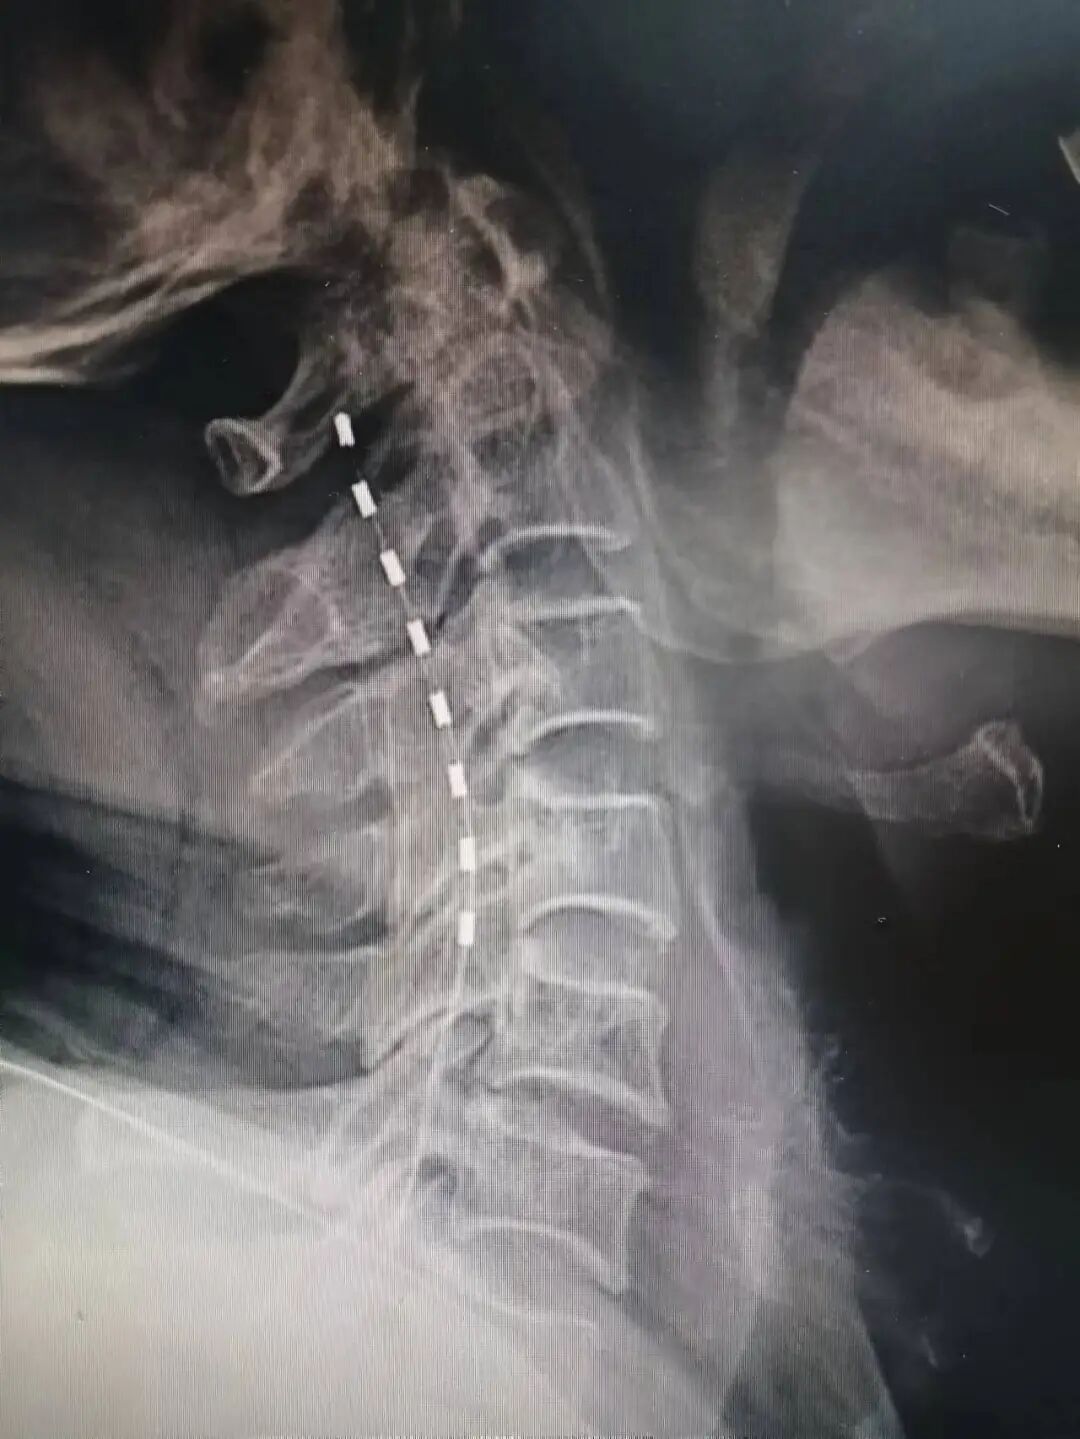

3.脊髓电刺激植入术

脊髓电刺激是一种先进的神经调控技术,通过将电极微创植入脊髓背侧,释放微弱电流干扰疼痛信号向大脑的传导,从而有效缓解顽固性神经病理性疼痛,尤其适用于复杂神经损伤痛。该技术具有可逆、可调、个体化等优势:患者可通过体外遥控器根据自身疼痛变化灵活调节刺激参数,实现个体化、动态的镇痛管理。

我院疼痛科于2022年1月成功实施江门地区首例脊髓电刺激植入术,为一位60岁饱受30余年神经痛及幻肢痛困扰的患者带来显著缓解;2024年8月,又率先完成五邑地区首例三叉神经半月节电刺激系统植入术,进一步拓展了神经调控技术在头面部顽固性疼痛中的应用,标志着我院在慢性疼痛微创与神经调控治疗领域持续走在区域前列。

△疼痛科为一名81岁左上肢急性带状疱疹神经痛患者行颈段脊髓电刺激术。